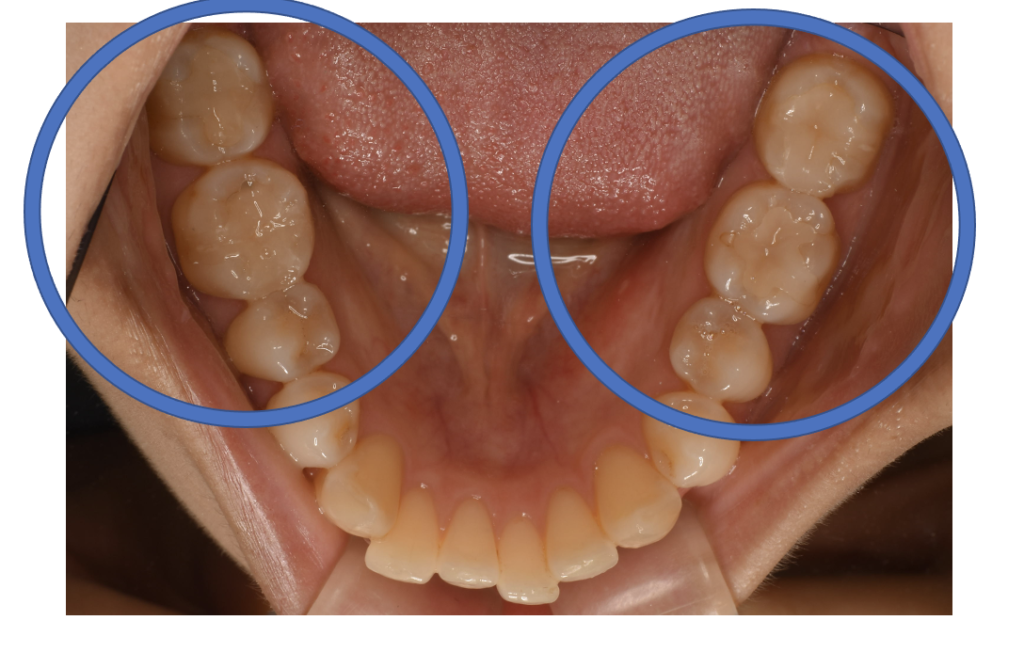

E-max In詰め物

E-max In 7 No.59

Before

After

| 治療方法 | セラミックインレー(E-MAX In) 虫歯などで失った歯質を天然歯と同じ色・質感のセラミックで補う治療法です。金属を使用する治療と比べて、審美性だけではなく、耐久性や体の負担が少ないという面でも優れていると注目されています。従来のセラミックと比べて天然歯と同程度の強度であり、耐久性が高くなっています。どのくらいもつかは使用状況や部位、メンテナンスの有無などによって大きく変わってきます。透明感があり、キレイで自然な色調を表現できます。歯と分子レベルの化学結合によって吸着するため隙間ができることが少なく、虫歯にもなりにくいと言われています。 そして、金属アレルギーのリスクがありません。 |

| 費用 | ¥69,000×3=¥207,000 |

| 通院回数 | 2週間〜1ヶ月 |

| 備考 | 院長より プラスティック修復部の内部に虫歯が進行してしまっていたケースです。中を開けて見てみると、外から想像するよりもはるかに虫歯が 広がってしまっていました。幸運にも神経を保存できたので、生きた臓器としてまだ使うことが可能です。今回は部分的な詰め物で対応することができたケースです。 |